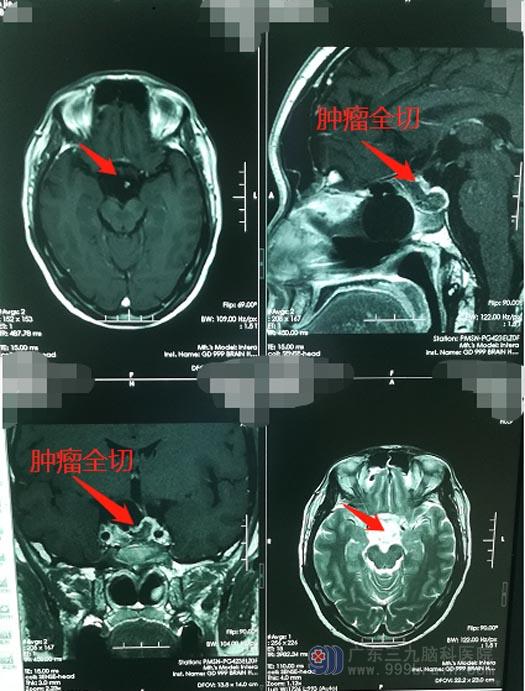

吴先生及家人得知病情后,同意进行手术治疗,由医院副院长、神经外五科主任鲁明主刀在全麻下行“内镜经鼻蝶垂体大腺瘤切除术”,手术过程十分顺利。术后不久吴先生就正常苏醒,两天后,吴先生感觉双眼视物清晰了很多,原本不戴眼镜根本看不清手机上的字,现在可以裸眼看手机了。